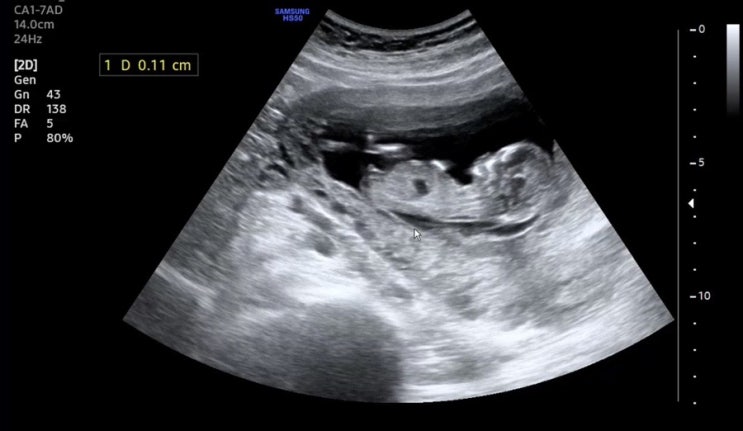

각도법은 과학인가 둘째도 아들 확정이다 ㅎㅎ 존재감 뿜뿜하는 17주1일차 초음파 - 내가 아둘맘이라니 허...